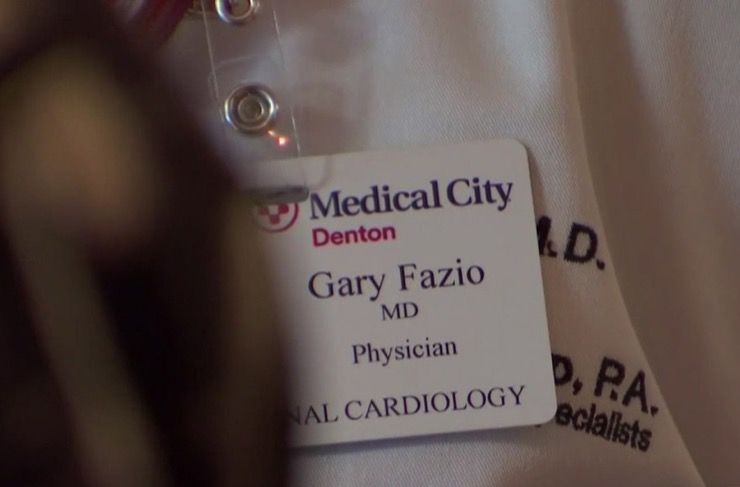

Cardiologist Dr. Gary Fazio was on call when Ed Burkett was brought in. He recalled that by the time Burkett actually arrived in the emergency room, he looked awful. Over the next harrowing hour, this particular patient would prove to even a veteran physician like Fazio what the human body is capable of.

It wasn’t until hours later that Dr. Fazio and his team were finally able to stabilize the former Navy man. This was after having to restart his heart a whopping 44 times. Still, they had done it, they had stabilized him. This was an impossible task and one that even Burkett’s worried relatives had not anticipated happening.

A Near Thing

It was a near thing to the end and one that Dr. Fazio considers nothing short of miraculous. “There are miracles that happen every day here,” he explained while talking to NBCDFW. The astonished doctor added that “Sometimes it takes someone like Ed to make it so obvious.” The incident wasn’t just miraculous, it was also unheard of.

44 Attacks, 20 Years

Dr. Fazio had been in medicine for more than 20 years and in two decades of working with patients and specifically the heart, he had never seen someone survive after 44 separate attacks. He had never come close to witnessing that kind of physical and emotional fortitude. “Generally speaking, after that many defibrillations, you’ve lost that battle,” he explained.

Great For Everyone

Dr. Fazio said that Burkett’s amazing story has lifted the spirits of staff and patients alike in his hospital. His story of survival is a reminder that where there is life, there’s hope. He adds that “if you have faith, anything is possible.” But Burkett is hardly the first cardiac patient to defy the odds in recent years.